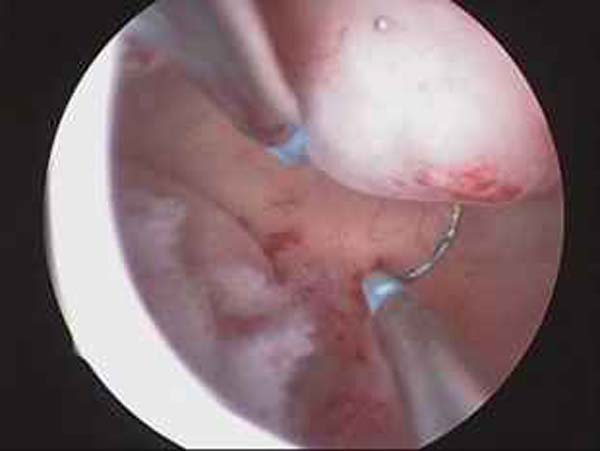

- Hystéroscopie - Hystéroscopie pour l'infertilité

- Résection hystéroscopique d'un septum utérin pour fausses couches à répétition

- Photos de l’hystéroscopie